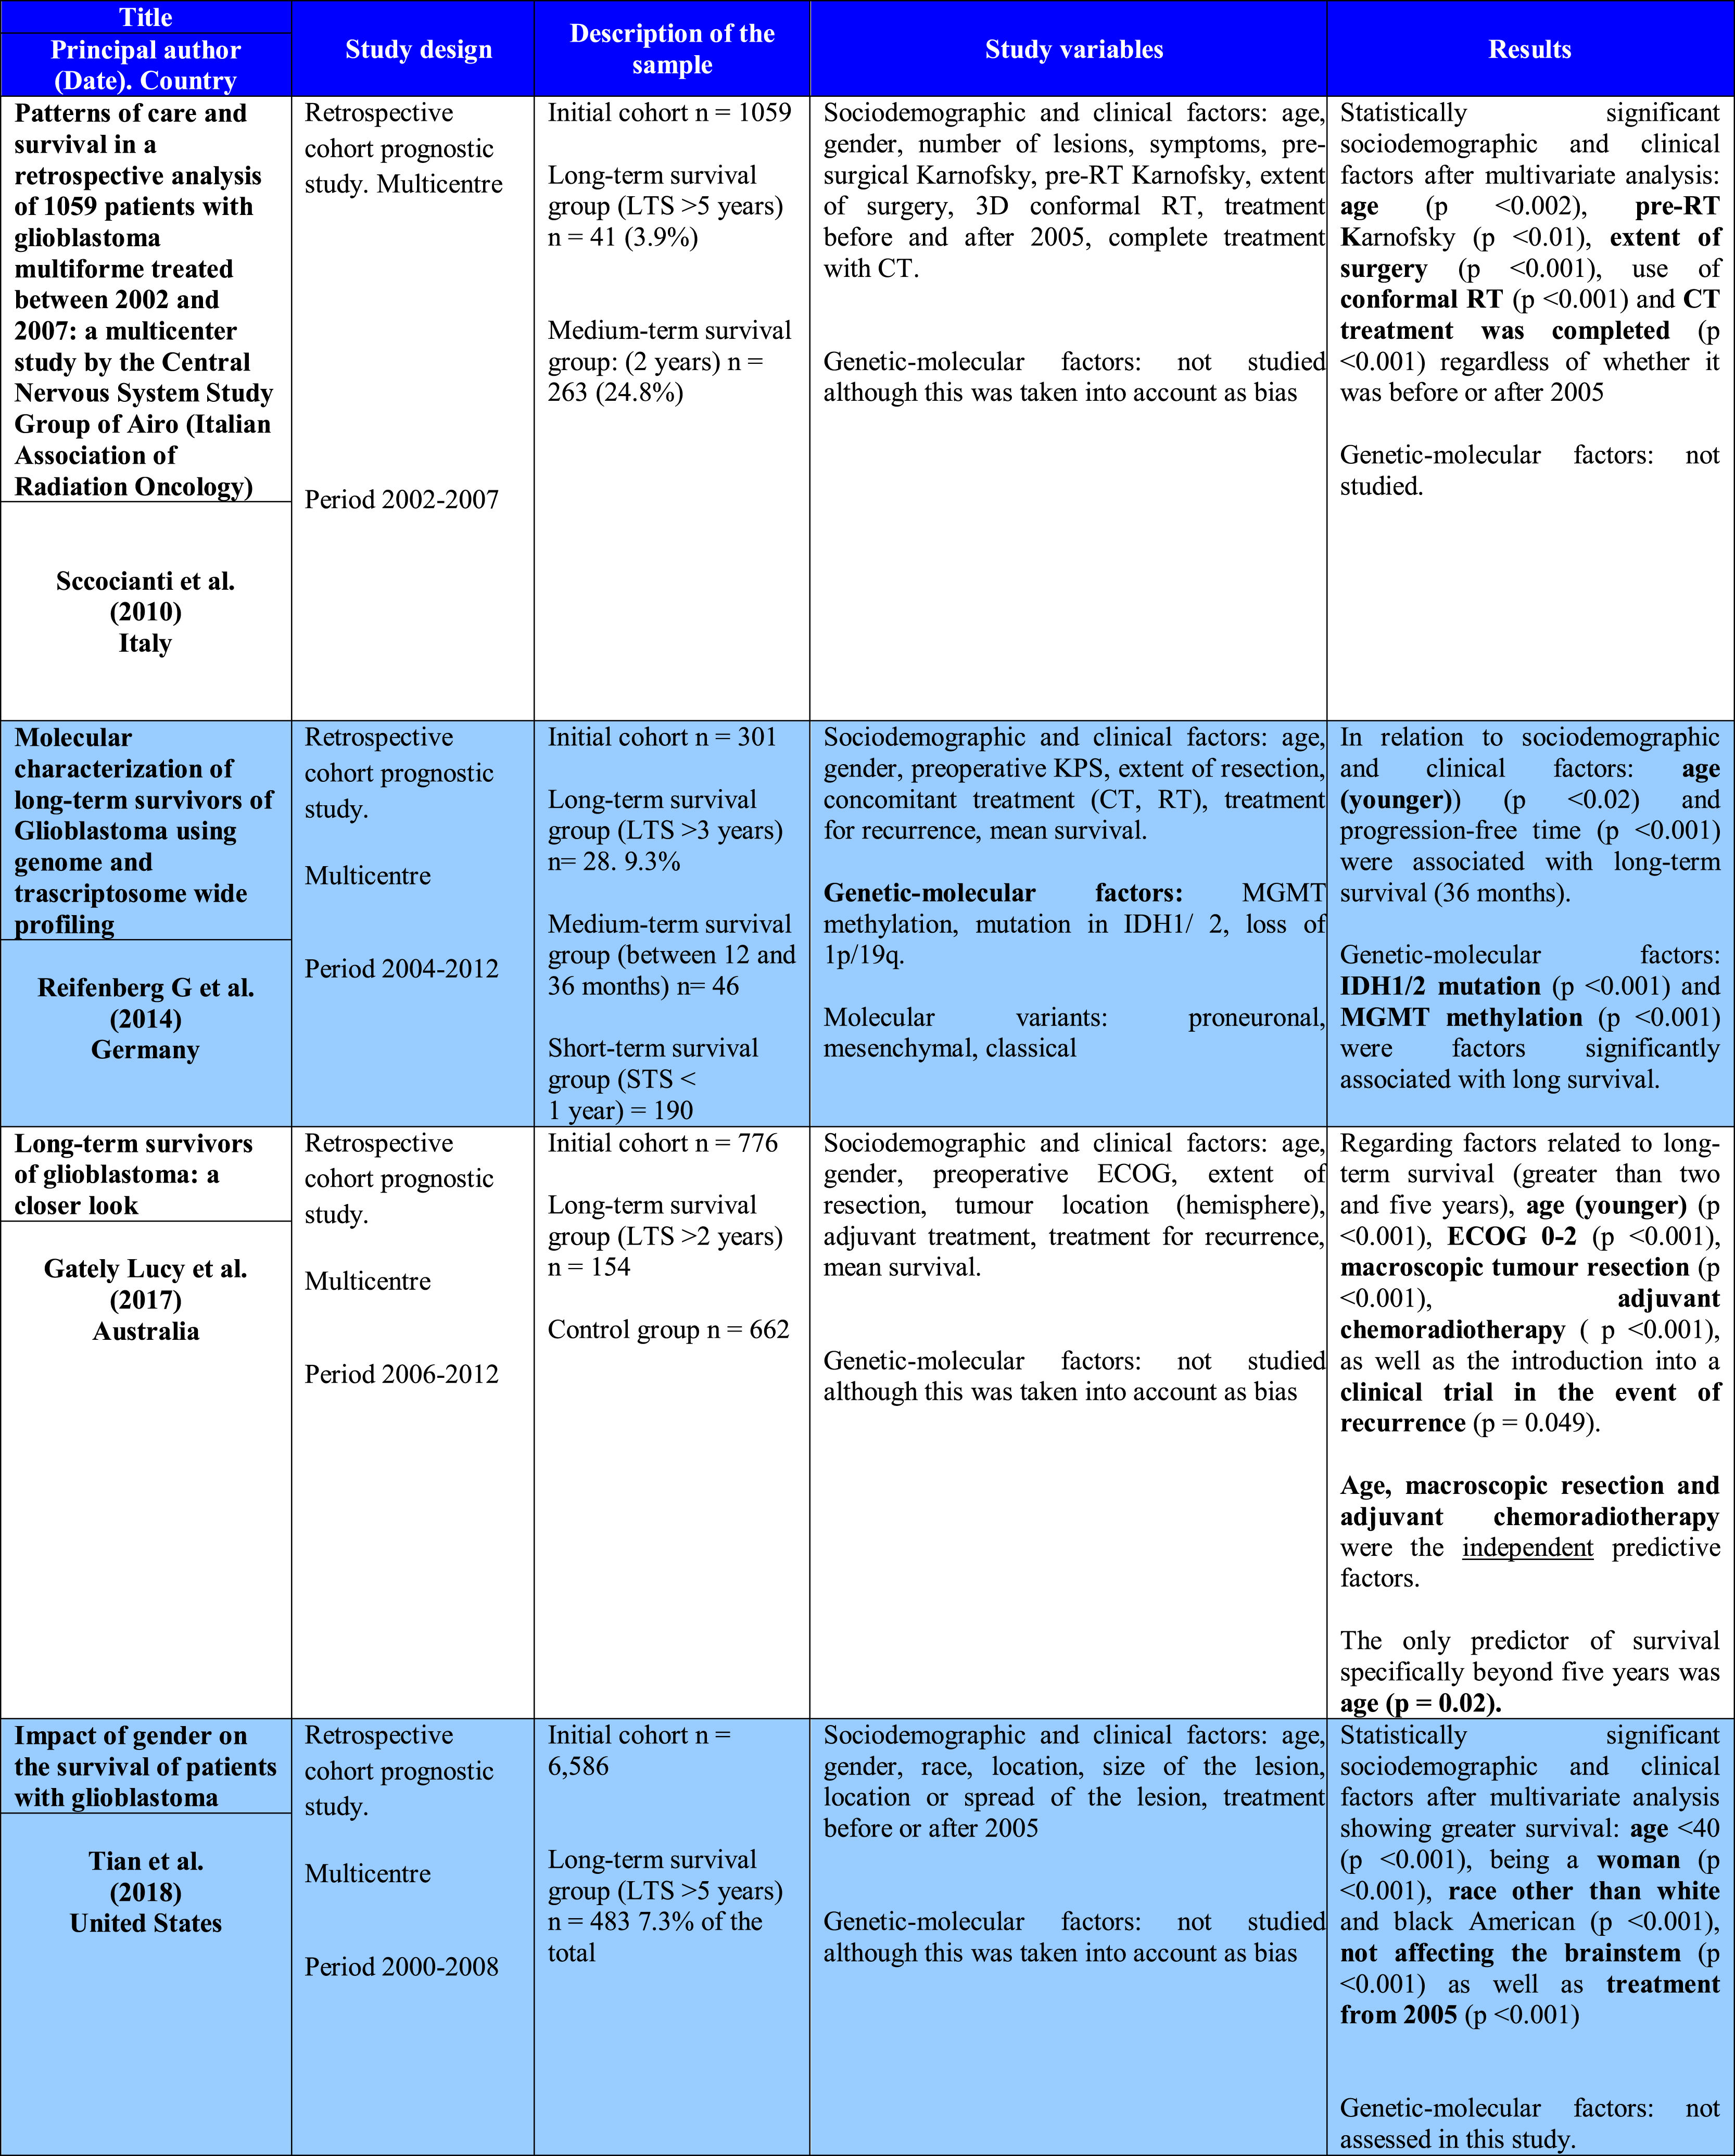

In spite of the changes for the treatment of glioblastoma since 2005, we have not seen differences between long-survival patients of more than 10 years showing a value minor than 1%.

Material and methodWe realize a systematic analysis and identify important factors for long survivor patients. We also show an own case with more of 20 years of survival. We make a new pathological study of the old paraffin block of this patient.

ResultsThe most important variable associated with long-survival between all multivariant studies is the age. When we try to find genetic and molecular alterations in glioblastoma associated with prolongated survival, the MGMT promoter methylation play the most important role. We find a correct diagnosis in the current analysis of our patient’s sample with very long survival.

ConclusionsMultiple variables are found that affect long survival of glioblastoma series but analyzed studies are very heterogeneous and it is very difficult comparation between them. Most articles we review are obtained from databases of different countries with hundreds of patients. It would be very interesting to promote the use of a single database in Spain that allows us to study these long-term glioblastoma survivors.